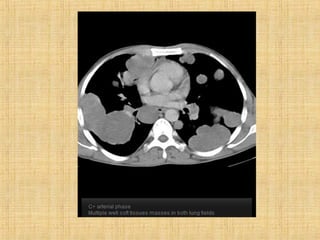

As principais informações do documento são: 1. Discute os padrões de doença pulmonar causados por metástases, incluindo nódulos, espessamento intersticial e obstrução das vias aéreas. 2. A prevalência de metástases pulmonares varia de 30-55% dependendo do tumor primário, e são mais comuns em pacientes acima de 50 anos. 3. Os achados clínicos mais comuns são dispneia, hemoptise e febre, enquanto exames de escarro ou lavado brô